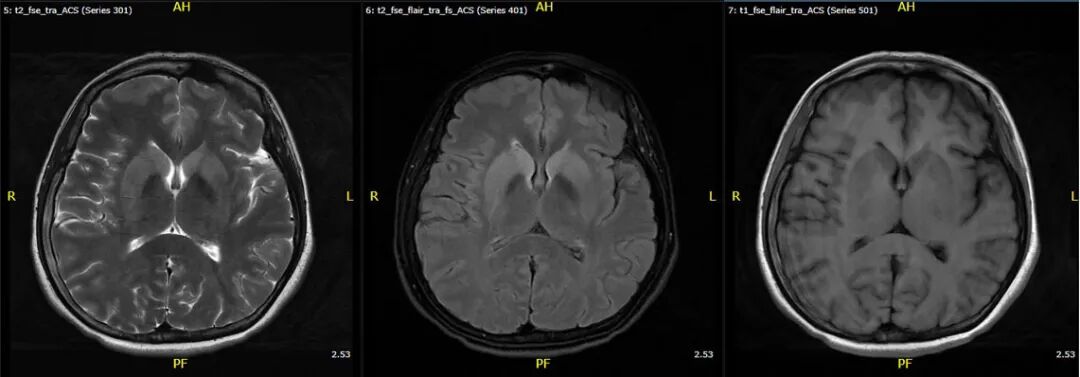

一切要从十几天前说起。患者最初因“发热11天、左臂麻木疼痛伴视物模糊5天”转入齐鲁医院神经内科。追溯病史,11天前她突发颈部淋巴结肿痛,伴有39.8℃的高热及呕吐腹泻,随之而来的是一种难以忍受的异常疼痛——轻触皮肤便如刀割一般,这种感觉很快蔓延至全身,同时双眼视力急剧下降。面对这些蹊跷的症状,神经内科副主任医师李怡通过查体和颅脑磁共振的特异性改变,迅速确定了大致诊疗方向,并完善了腰穿、脑脊液病原体NGS、自身免疫抗体等一系列辅助检查。